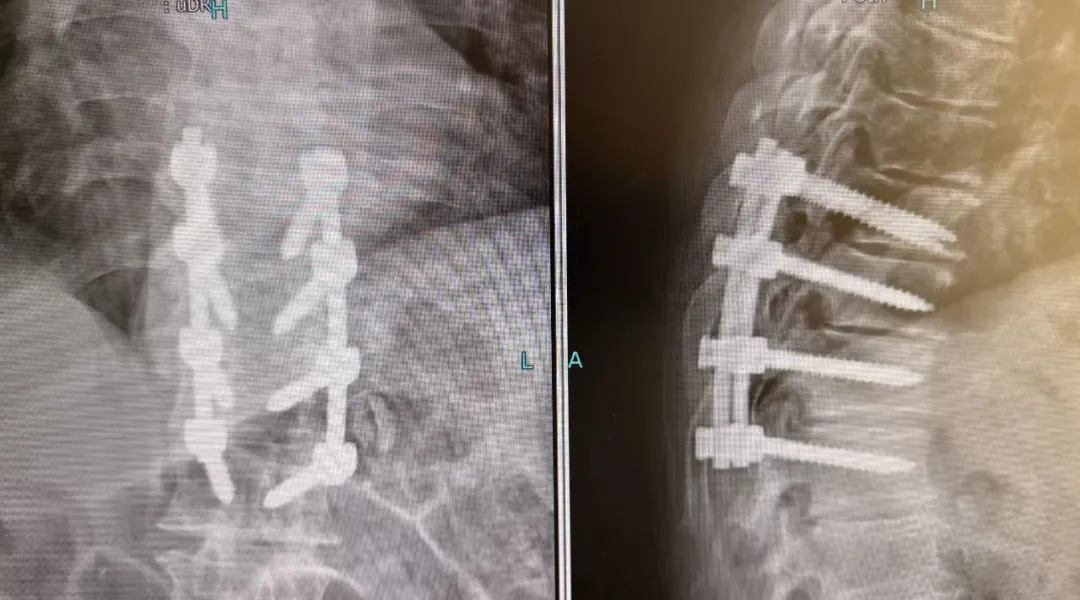

在麻醉科及护理团队的有力保障下,由韦竑宇主刀的骨科团队成功为老人实施了后入路胸椎管切开减压、植骨融合、椎弓根螺钉内固定术。